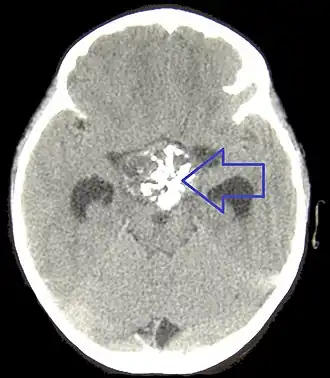

Для диагностики гипопитуитаризма у взрослых важнейшее значение имеют данные анамнеза (операции и облучение гипофиза, осложненные массивным кровотечением роды и т. д.). При гормональном исследовании определяется сочетание низких уровней гормонов периферических эндокринных желез (Т4, тестостерон, эстрадиол, кортизол) со сниженными или низкими уровнями тропных гормонов и гормона роста. В большинстве случаев необходимо подтверждение дефицита тропных гормонов и гормона роста в стимуляционных пробах. Всем пациентам показано проведение МРТ головного мозга.